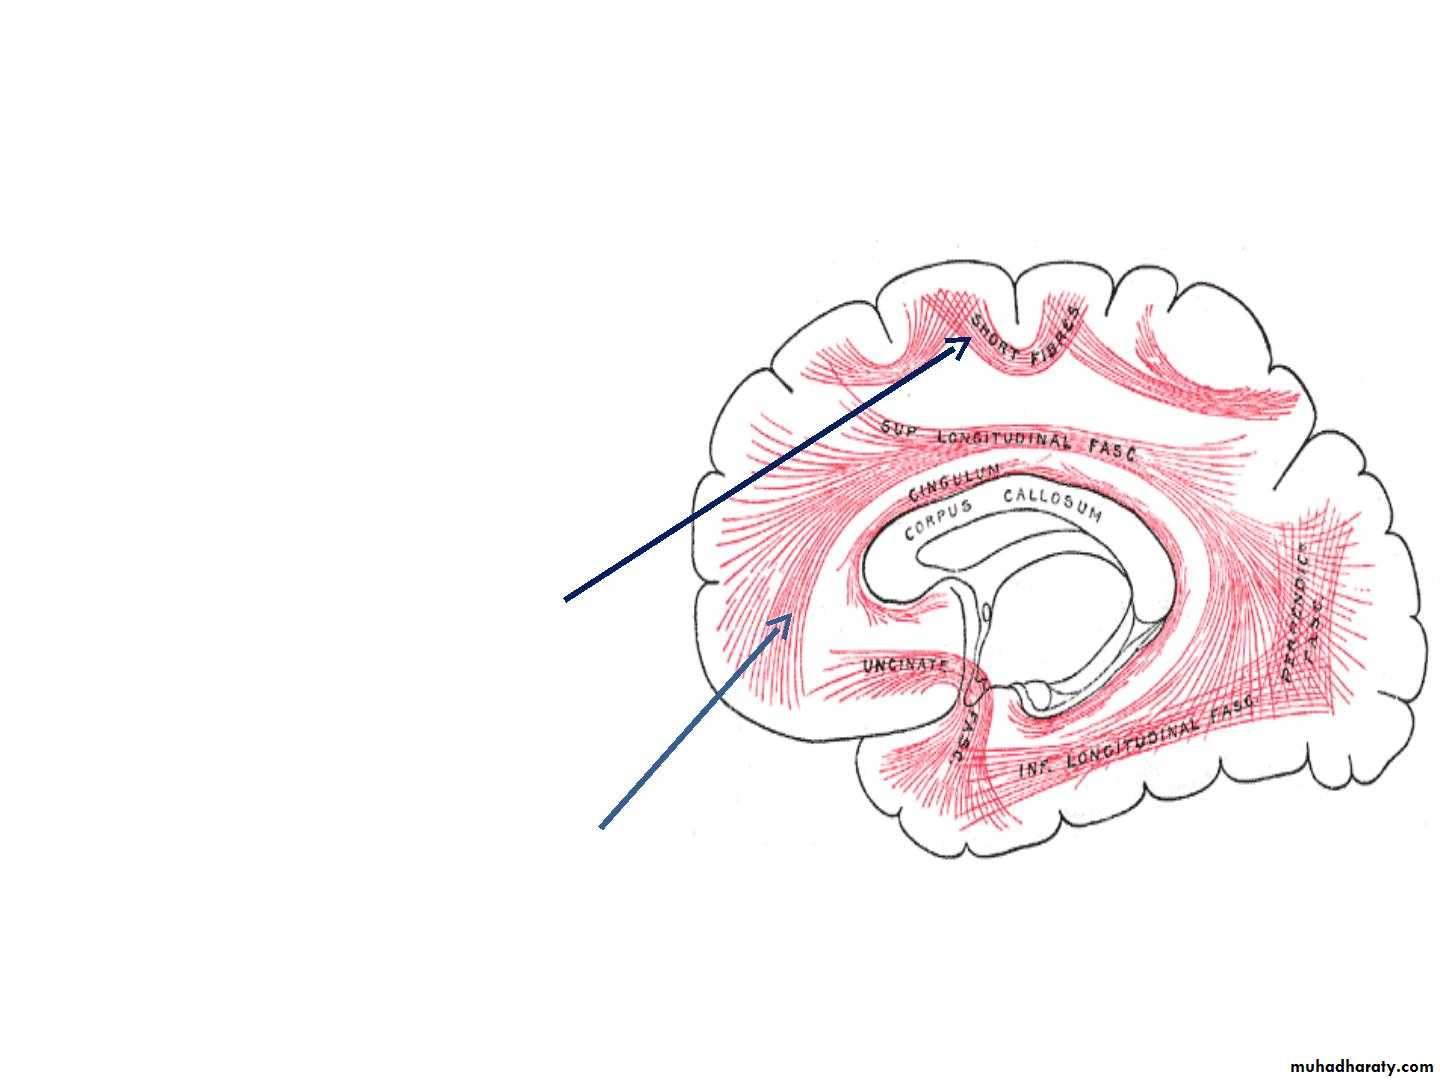

• 2. Association Fibers :

• • Association fibers are nerve fibers that• essentially connect various cortical regions

• within the same hemisphere and may be

• divided into :

• A. The shorT associaTion fibers

• B. The long associaTion fibers :

• B. Association fibres

• • It links different cortical areas

• of the same hemisphere

• • Two types

• v. Short association fibres

• They are entirely intracotical

• Some merely pass from one

• wall of the sulcus to other.

• viii.Long association fibres

• They are present in bundles

• Example: uncinate

• fasciculus,cingulum,superior

• longitudinal fasciculus,etc